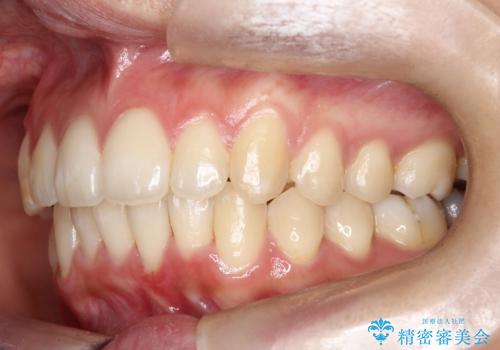

驚くほど短期間で前歯のガタツキを解消! マウスピース矯正の効果

- 前歯のでこぼこが気になると来院されました。

マウスピース矯正治療を選択しました。

奥歯の噛み合わせは綺麗に噛んでいたため、前歯の叢生(でこぼこ)を、短期間で治療完了するように計画しました。

奥歯の噛み合わせは整っていたため、前歯の並びを美しく修正することに専念できました。マウスピース矯正による治療で短期間で改善しました。

前歯のガタツキを改善する治療法として、マウスピース矯正が適していることが多いです。